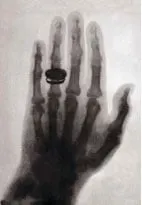

你知道第一屆諾貝爾物理學獎是誰獲得的嗎?答案是威廉·倫琴(Wilhelm Conrad Röntgen),他於1895發現了一種特殊的射線,並將這種射線命名為X光,他發現了這個射線穿透人體後會在底片上顯影,有傳言說:起初他還以為這是一種來自撒旦的妖術,因此不敢公開自己發現的結果,經過倫琴夫人勸說後他才願意公開自己的研究。他的發現為科學界帶來了一種「可能性」,一種探究未知的可能性,而自此,11/8便成了大家公定的「放射師節」。